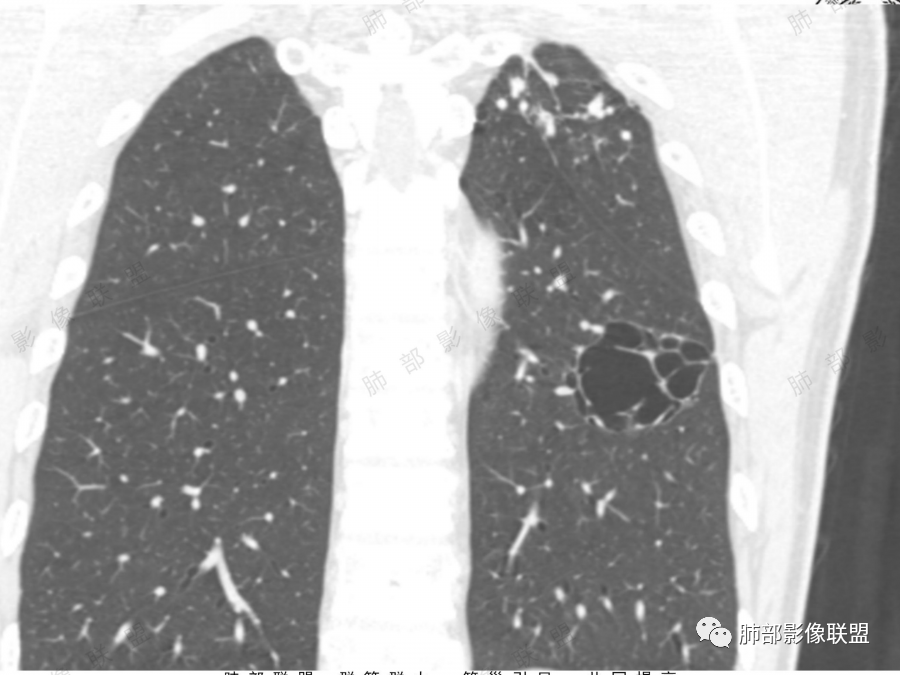

左肺下叶空腔,分隔状,壁厚薄不均,支气管截断,部分周围可见磨玻璃影,胸膜牵拉,左肺上叶多发结节,部分可见钙化,考虑1左肺下叶囊腔型腺癌。2左肺上叶结核。

男51,体检发现肺部阴影,左肺下叶见多发薄壁囊腔影,可见结节,囊腔内见分隔,轻度胸膜牵拉,病灶周围少许磨玻璃影,常规考虑囊腔型腺癌,肿瘤标志物不高,除外结核。

中年男性,体检发现,吸烟史,但肺气肿背景不明显。左肺下叶囊腔病变,有一定张力,分隔明显,似有多个囊腔融合感,部分边缘见少许磨玻璃影,有支气管截断,首选囊腔型肺癌,某些先天病变(囊腺瘤样畸形等)也要考虑。

老年,51岁男性病人,左上肺斑点,小结节状阴影,可见钙化,陈旧性肺结核改变,患者有长期的吸烟病史。左肺下叶背段多个囊腔肿块影,整体呈团块状类圆型,无明显壁结节,整体病灶张力较大,具备一定的膨胀感 ,支气管拉直并有突然截断改变,考虑囊腔型鳞癌。鉴别诊断:结核性病变,局限性囊性支气管扩张

男性,体检发现左肺阴影。影像表现:左上肺多发结节伴纤维条索影,部分钙化,左下肺囊腔样改变,内有分隔,部分分隔边缘见实性成分及GGO样改变,支气管从旁边经过,或受压,无明确进入依据。初步诊断:1、左上肺结核。2、左下肺囊腔型腺癌,诊断依据:分隔样囊腔,部分分隔有实变,边缘有GGO改变,鉴别诊断:1、囊腺瘤样畸形,分隔样囊腔要考虑,但部分分隔实变,部分伴GGO样改变成疑,最大的疑问是年龄51岁,体检发现,抽烟、饮酒30年,却无发病,可能性太小。2、囊腔性转移,单发分隔样囊腔转移少见,且需要病史支持。3、囊性淋巴瘤,一般以单发囊腔多见,分隔样囊腔型淋巴瘤罕见。4、感染,无相关临床症状及辅检支持,基本排除。

孤立性的多囊型病变伴分隔。ccam,肺隔离征,囊性肺癌,闭锁。。这是大家上面写的。看看怎么排除。血管看到肺动脉进入供血,没有感染液平,肺隔离不符合。没有代偿肺气肿,支气管没有闭锁,闭锁不考虑。那锁定ccam和肺癌。我们临床也常见是支气管畸形所致的囊。

我们看哪些内容,第1.周围有没有毛玻璃2.分隔有无粗细不均或结节,壁有无厚薄不均有无壁结节3.支气管,4.随访。